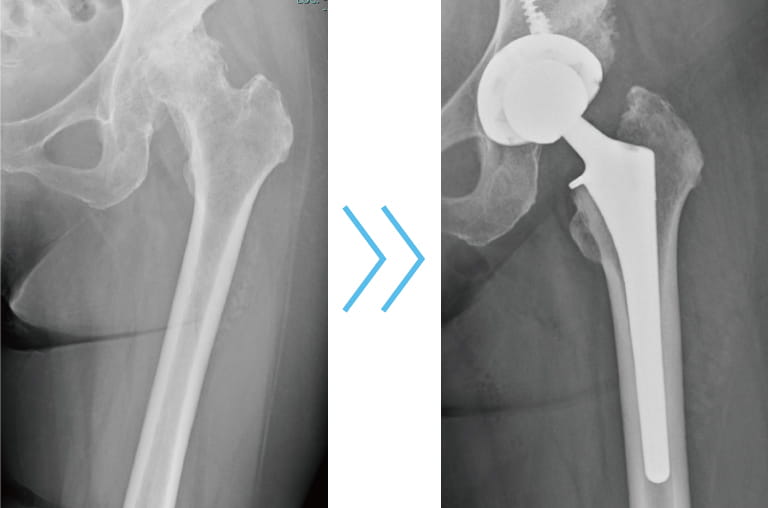

人工股関節置換術(THA)とは

変形性股関節症や大腿骨頭壊死症、関節リウマチの股関節病変など様々な疾患のために股関節に著しい障害が起こり、痛みや動きづらさで日常生活に支障が出てくる場合があります。そのような場合に、その障害のある関節を金属やセラミック、ポリエチレンなどでできた人工関節に入れ替えることで、痛みがなくなり、歩行能力が改善されます。

人工股関節置換術(THA)担当医師

佐賀大学医学部整形外科の馬渡 正明名誉教授のご協力のもと、人工股関節置換術(THA)を定期的に行っています。安定した治療結果が得られており、「生活の質を上げる」こともできるため、人工股関節置換術を希望される方も増えてきています。